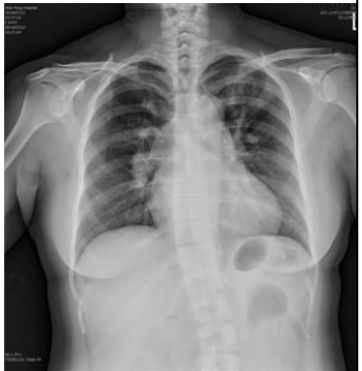

5. 病人男性59歲於午夜24時,突因胸悶並有牙床緊疼,乃直往急診部求診,時病人之T/P/R = 35.1/51/18, BP 137/74 mmHg; 理學檢查,未見任何異常。病史追尋,本病人曾經醫師確定高血壓、高脂血、糖尿病及攝護腺肥大,唯僅只服用Bisoprolol 2.5 mg/day。經緊急檢查:其心電圖及胸部X光顯示如圖:生化檢查: CK,96 U/L;CK-MB,20 U/L;TnI <0.0012 ng/ml;Sugar 252 mg/dL; Na,137 mmol/L; K, 3.7 mmol/L; TG,182 mg/dL and Total cholesterol, 222 mg/dL ; 血液檢查: Hb,13.9 g/dl; Platelet, 203 K/uL; WBC,9.45 K/uL; Cre,1.3 mg/dL 請問本病人最可能的急診診斷是:

(A) Printzmetal's angina (B) Aortic dissection (C) Acute anterior myocardial infarction (D) Hypertension (E) Acute periodontitis disease